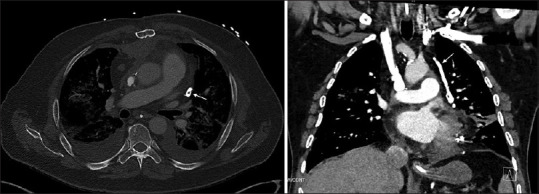

Misplacement of a Left Internal Jugular Central Venous Catheter in the Pericardiophrenic Vein.